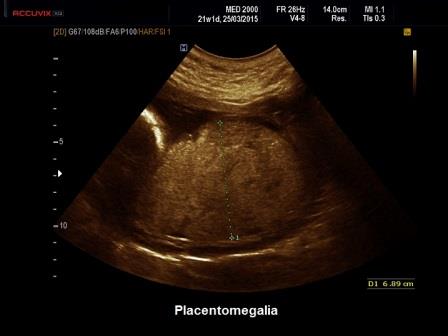

Il normale spessore della placenta viene calcolato considerando che la placenta cresce di spessore di circa 1 mm. a settimana. Un aumento di spessore della placenta si diagnostica se lo spessore della placenta supera i 4 cm. nel corso del II trimestre e i 6 cm. nel corso del III trimestre (Norton ME et al. Callen Ultr Obst Gyn 19:685-715. Elsevier 2017)

Un

aumento di spessore della placenta (Placentomegalia) può

riconoscere varie cause che vengono distinte in due categorie in base alla ecostruttura: